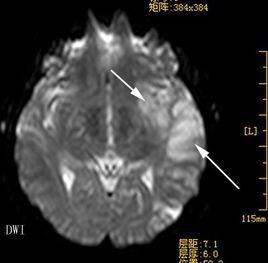

MRI可清晰顯示早期缺血性梗死、腦幹及小腦梗死、靜脈竇血栓形成等,梗死後數小時即出現T1低信號、T2高信號灶,出血性梗死顯示其中混雜T1高信號。釓增強MRI較平掃敏感。功能性MRI彌散加權成像(DWI)可早期診斷缺血性卒中,發病2小時內即顯示缺血病變,為早期治療提供重要信息。DSA可發現血管狹窄及閉塞部位,顯示動脈炎、Moyamoya病、動脈瘤和靜脈畸形等。